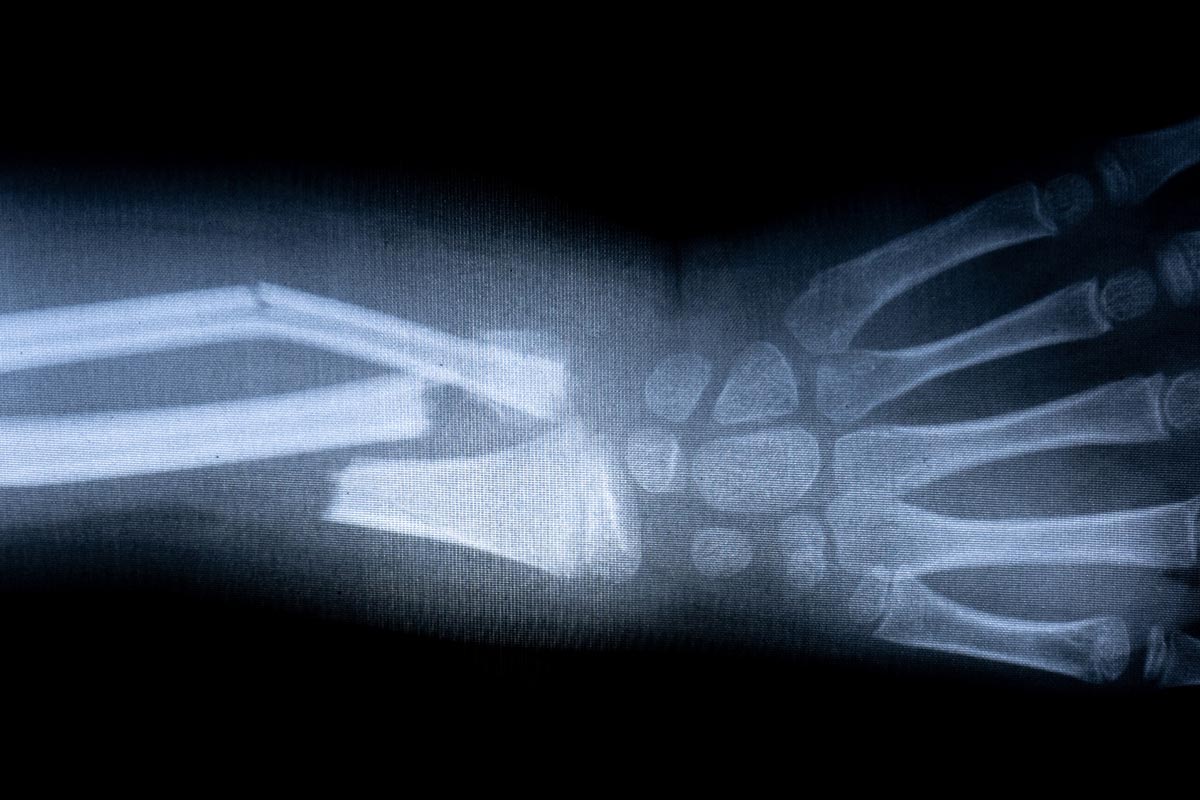

ZŁAMANIE KOŚCI PRZEDRAMIENIA

Przedramię składa się z dwóch kości: promieniowej i łokciowej. W większości przypadków złamania w obrębie przedramienia dotyczą obu kości jednocześnie. Złamanie może dotyczyć jednego miejsca kości bądź wielu jej fragmentów. Złamanie, które nie przebija powierzchni skóry nazywamy złamaniem zamkniętym. Natomiast, gdy kość w trakcie urazu przebija skórę jest to złamanie otwarte, które jest wysoce niebezpieczne ze względu na duże ryzyko infekcji. Do złamań w obrębie przedramienia zazwyczaj dochodzi na skutek bezpośrednich uderzeń, upadku na wyprostowaną rękę lub w wyniku wypadków komunikacyjnych. Złamania przedramienia nie da się nie zauważyć. Ręka drastycznie puchnie, sinieje, pojawia się ogromny ból, a jej ruchomość jest równa zeru.

Złamania otwarte leczy się tylko chirurgicznie. W złamaniach zamkniętych możliwe jest leczenie zachowawcze. Natomiast, niezależnie od wybranego przez lekarza sposobu leczenia, ważne jest prawidłowe unieruchomienie. Z racji tego, że przedramię łączy nadgarstek z łokciem, to de facto jego prawidłowe unieruchomienie jest możliwe tylko poprzez unieruchomienie tych dwóch stawów. Dodatkowo, w przedramieniu dochodzi do ruchu obrotowego (rotacji), w wyniku którego kość promieniowa obraca się względem kości łokciowej. W przypadku złamania, ruch rotacji jest niemożliwy i konieczny do wyeliminowania. Jest to możliwe poprzez zastosowanie profesjonalnej ortezy kończyny górnej takiej jak AM-SL-03, która pozwala na unieruchomienie stawu promieniowo-nadgarstkowego i zniwelowanie ruchu rotacji przedramienia. Dodatkowo, orteza zapewnia możliwość ustawienia konkretnego kąta rotacji przedramienia oraz odwiedzenia odłokciowego lub dopromieniowego nadgarstka.

Przedramię składa się z dwóch kości: promieniowej i łokciowej. W większości przypadków złamania w obrębie przedramienia dotyczą obu kości jednocześnie. Złamanie może dotyczyć jednego miejsca kości bądź wielu jej fragmentów. Złamanie, które nie przebija powierzchni skóry nazywamy złamaniem zamkniętym. Natomiast, gdy kość w trakcie urazu przebija skórę jest to złamanie otwarte, które jest wysoce niebezpieczne ze względu na duże ryzyko infekcji. Do złamań w obrębie przedramienia zazwyczaj dochodzi na skutek bezpośrednich uderzeń, upadku na wyprostowaną rękę lub w wyniku wypadków komunikacyjnych. Złamania przedramienia nie da się nie zauważyć. Ręka drastycznie puchnie, sinieje, pojawia się ogromny ból, a jej ruchomość jest równa zeru.

Złamania otwarte leczy się tylko chirurgicznie. W złamaniach zamkniętych możliwe jest leczenie zachowawcze. Natomiast, niezależnie od wybranego przez lekarza sposobu leczenia, ważne jest prawidłowe unieruchomienie. Z racji tego, że przedramię łączy nadgarstek z łokciem, to de facto jego prawidłowe unieruchomienie jest możliwe tylko poprzez unieruchomienie tych dwóch stawów. Dodatkowo, w przedramieniu dochodzi do ruchu obrotowego (rotacji), w wyniku którego kość promieniowa obraca się względem kości łokciowej. W przypadku złamania, ruch rotacji jest niemożliwy i konieczny do wyeliminowania. Jest to możliwe poprzez zastosowanie profesjonalnej ortezy kończyny górnej takiej jak AM-SL-03, która pozwala na unieruchomienie stawu promieniowo-nadgarstkowego i zniwelowanie ruchu rotacji przedramienia. Dodatkowo, orteza zapewnia możliwość ustawienia konkretnego kąta rotacji przedramienia oraz odwiedzenia odłokciowego lub dopromieniowego nadgarstka.